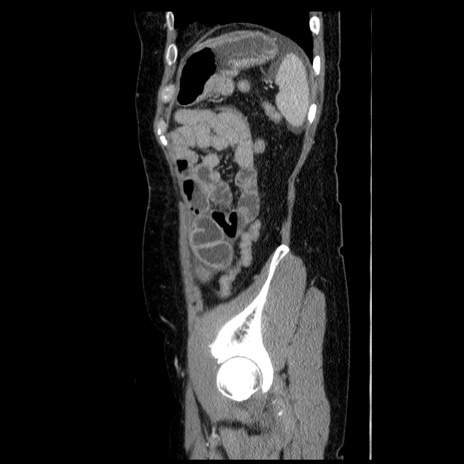

症例6(矢状断像)

【症例】50歳代女性

【主訴】下腹部痛

【現病歴】本日朝より下痢2回あり。 昼食を食べた後、嘔吐3回、下腹部痛認め、症状軽快せず、当院救急搬送。

最終食事:本日昼(生ものなし)。 昨日の夜、刺身を食ぺたとのこと。周囲に同様の症状の者なし。普段、排便は毎日あるとのこと。

【既往歴】卵巣癌術後(8年前に当院で卵巣摘出)

【身体所見】 意識清明、腹部:平坦、腸蠕動音→、やや硬、下腹部自発痛・圧痛あり、反跳痛あり、筋性防御なし。

【データ】WBC 16000、CRP 0.01